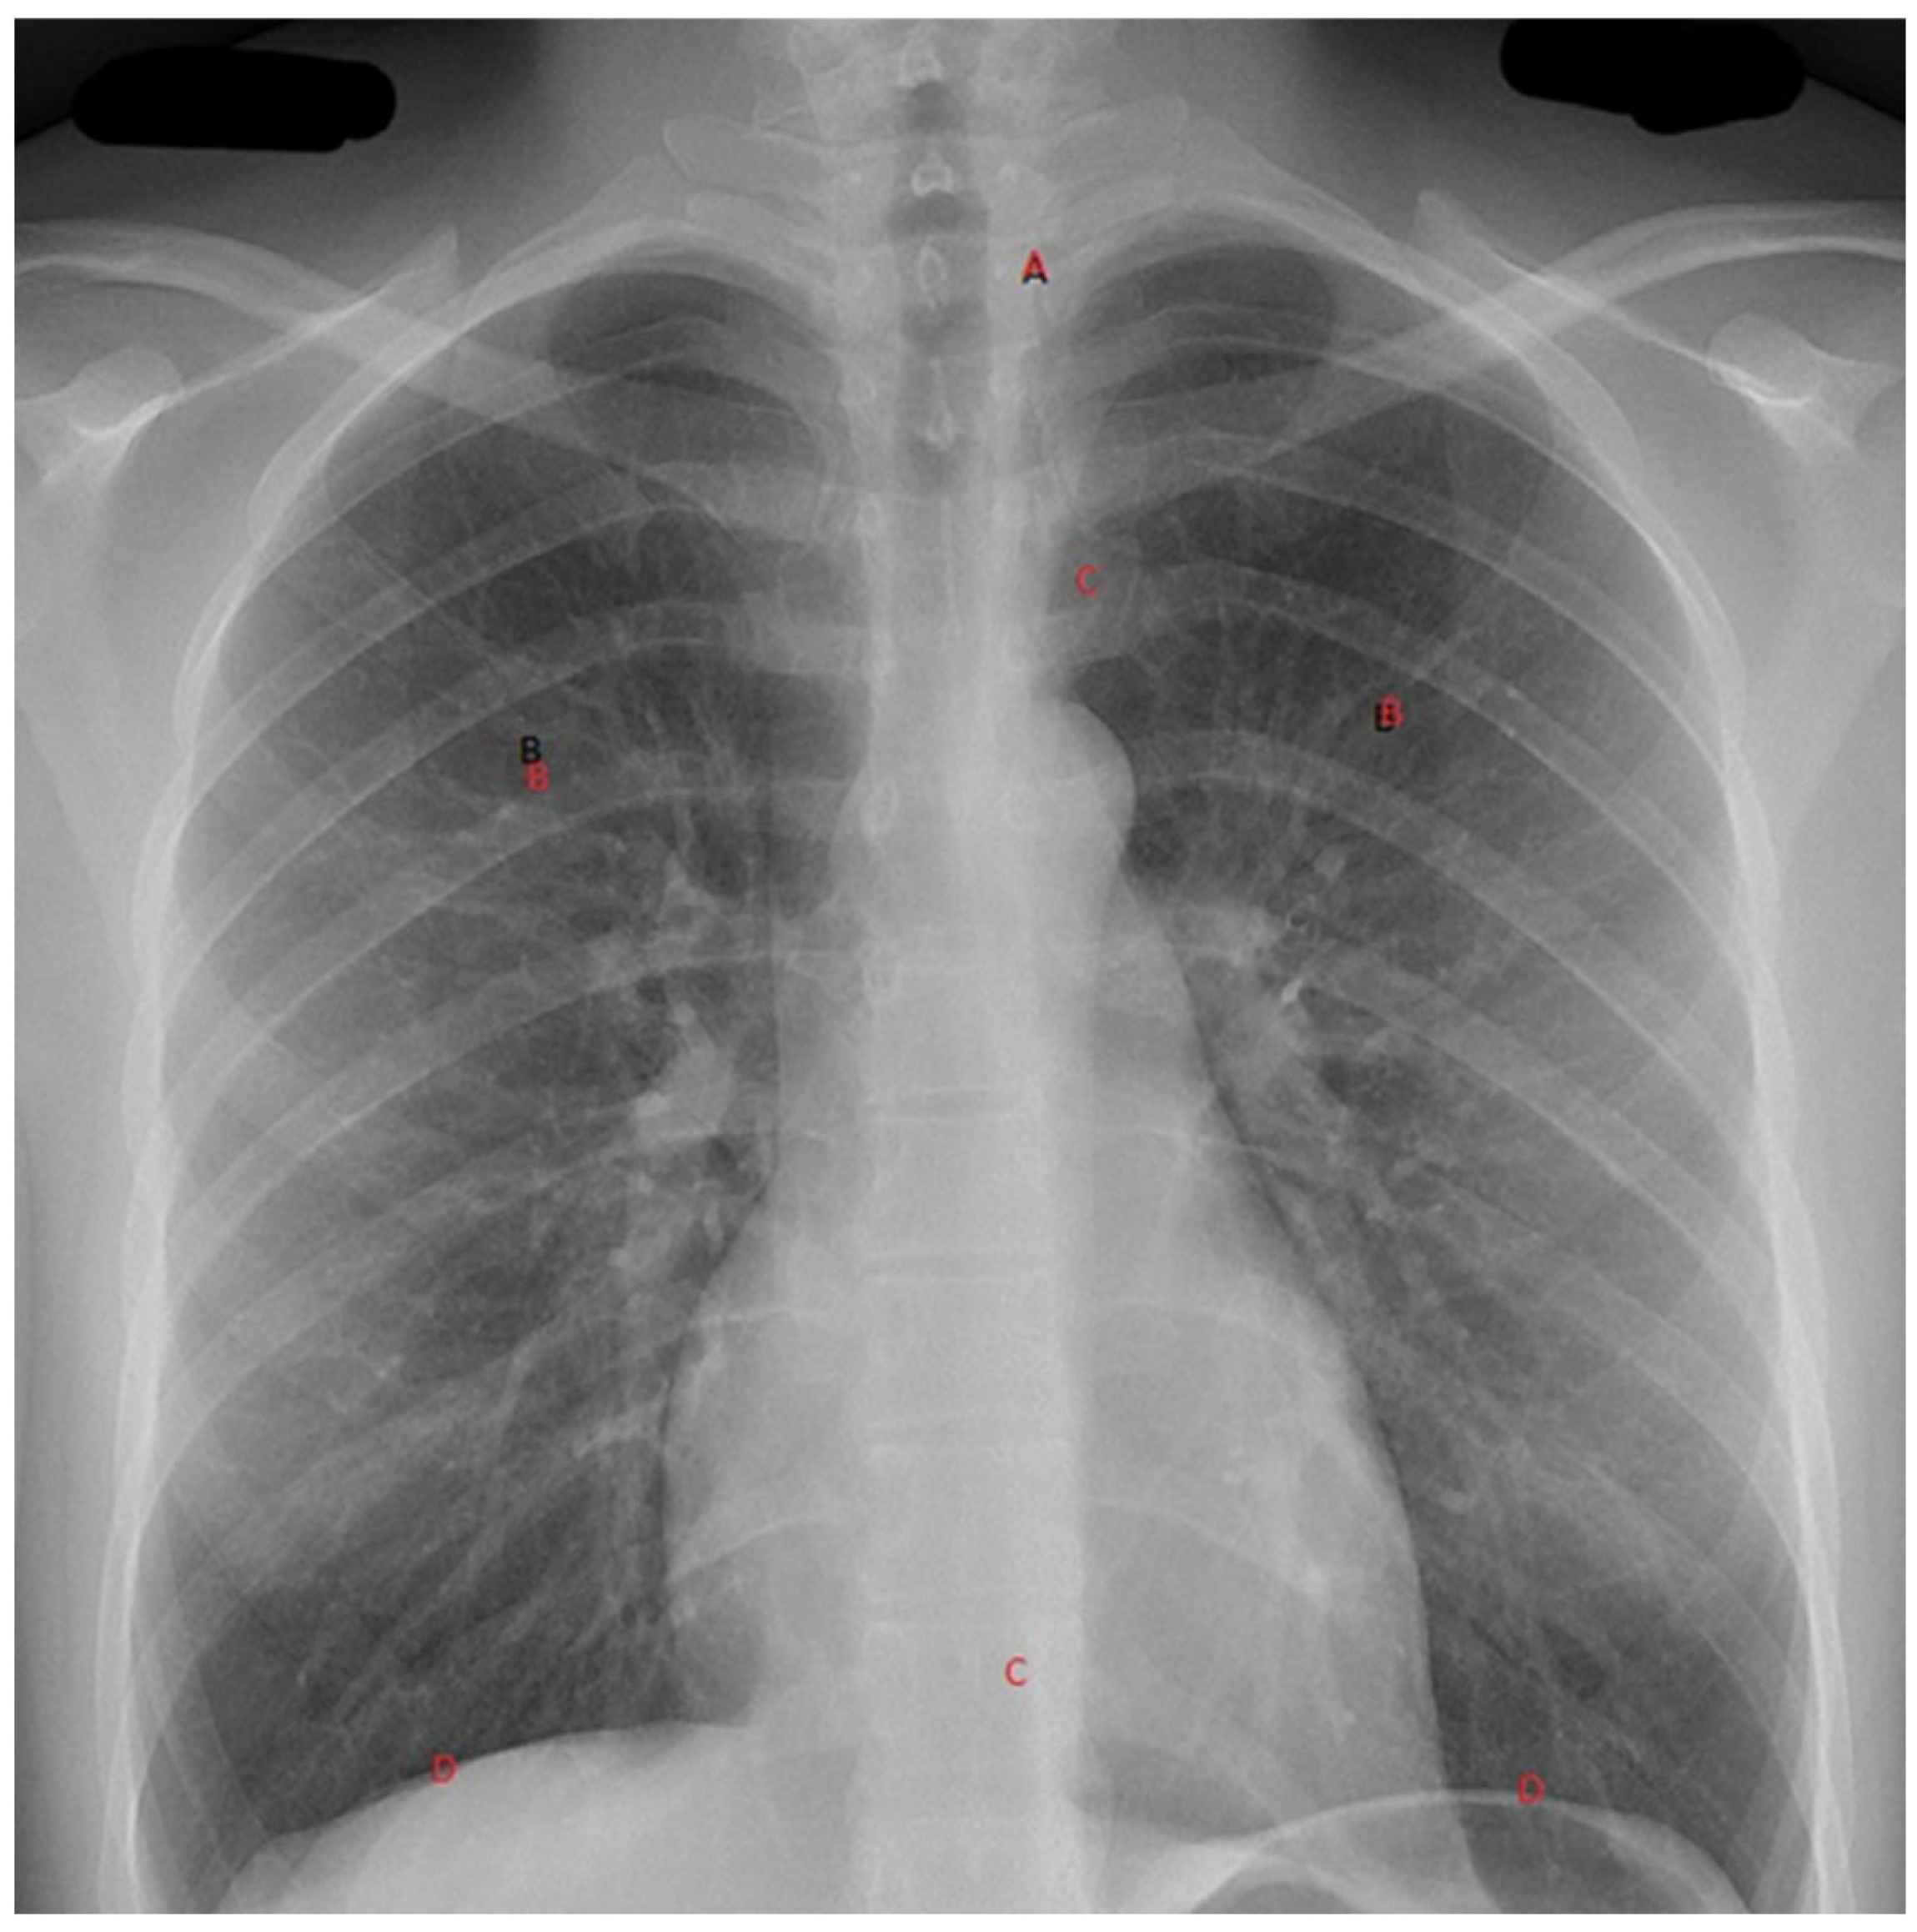

With these devices comes the need to ensure a reliable interpretation of the images obtained. Adopting a clinician-based reporting system to assess radiographs will allow an interpretation of these X-rays to optimize the identification of pathologies and the minimization of missed diagnoses. For C-spine X-rays, in interpreting a lateral c-spine X-ray, the following system may be adopted: adequacy (C1 to top of T1), check the alignment along four lines (namely: A, Anterior vertebral line; B, Anterior spinal line; C, Posterior spinal line; and D, Spinous processes). For the Chest X-ray, a recommended system for interpreting a plain AP Chest X-ray would follow an ABCDEF approach (illustrated in Figure 3): Airway, which is the position of the trachea and of an endotracheal tube if present; Breathing, which includes a lung-field assessment, looking specifically for haemothorax, pneumothorax, and contusions; Circulation, where mediastinal width, heart shape, and size are assessed; Diaphragms; any Extras, including anything that is visible e.g., ECG electrodes, Nasogastric tubes, etc.; and Fractures, the examination of which follows a system from medially to laterally, from the ribs (anterior and posterior), to the clavicle, to the scapulae humerus, and to the vertebrae, if visible. A similar system can be used for the pelvis, limbs, and the vertebrae plain X-rays as well.

Figure 3.

The ABDCEF approach to viewing a chest X-ray.